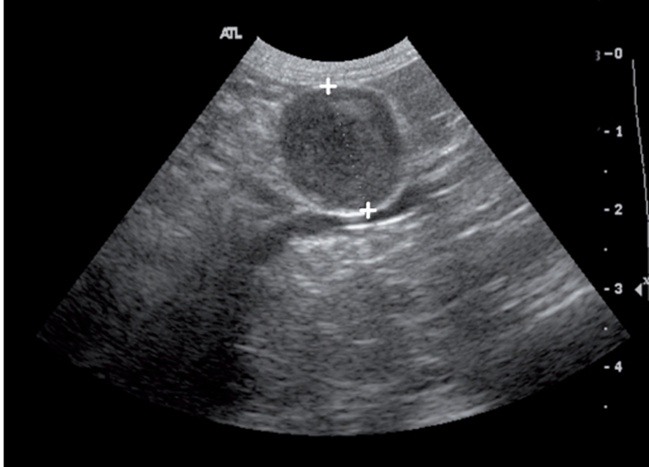

실습을 통하여 데일리벳 커뮤니티의 부신을 관찰하고 측정한 그림입니다(그림 4).

데일리벳 커뮤니티에서는 좌측 부신은 대동맥에서 신장동맥보다는 전장간막동맥을 이정표로 하면 쉽게 찾으며, 우측 부신은 우측 신장의 약간 앞쪽 위치의 CVC에서 찾으면 쉽게 찾게 됩니다(7).

이때 보이는 데일리벳 커뮤니티의 모양은 개와 달리 난원형(oval shape)이나 개에서와 비슷한 두 개의 엽 모양(bilobed shape)으로 보이며, 실질은 저에코성으로 보입니다.